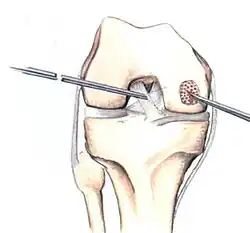

If non-surgical measures are unsuccessful, drilling may be considered to stimulate healing of the subchondral bone. Arthroscopic drilling may be performed by using an antegrade (from the front) approach from the joint space through the articular cartilage, or by using a retrograde (from behind) approach through the bone outside of the joint to avoid penetration of the articular cartilage. This has proven successful with positive results at one-year follow-up with antegrade drilling in nine out of eleven teenagers with the juvenile form of OCD,[53] and in 18 of 20 skeletally immature people (follow-up of five years) who had failed prior conservative programs.[54]